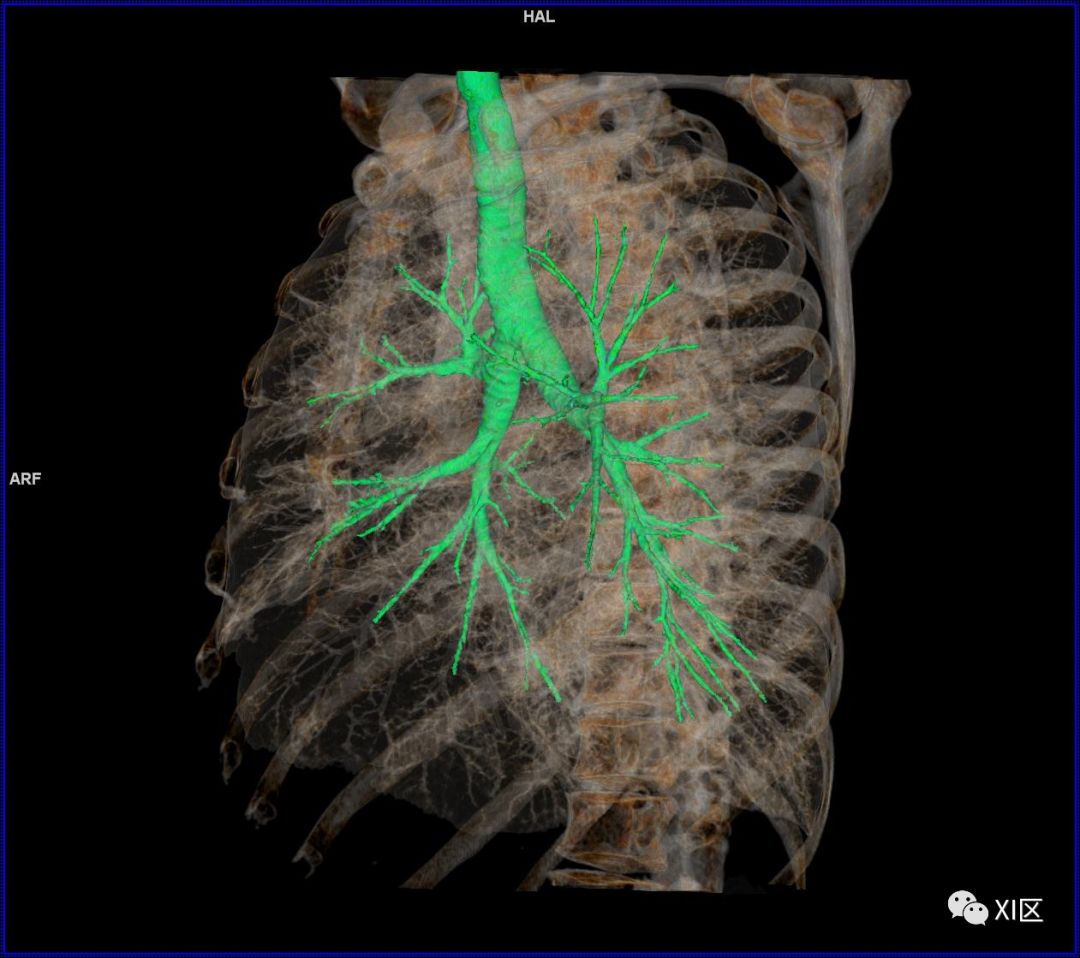

前后位,双侧位,后前位显示气道肺与胸部骨骼的关系

气管树与胸部其他结构的关系